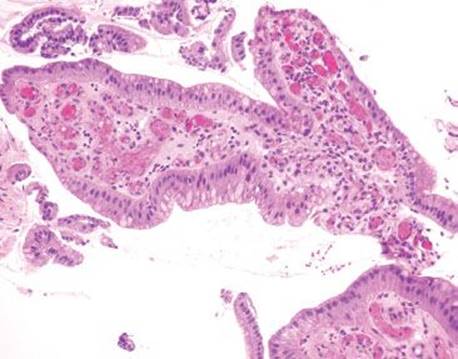

Figure 2.211 PHG. On higher power, the congested vessels are more easily seen. A chart review revealed a history of portal hypertension, and a diagnosis of portal hypertensive gastropathy was rendered. This case is an excellent example of pushing through the first obvious diagnosis (reactive gastritis/gastropathy pattern) and thoroughly searching for other important diagnoses (portal hypertensive gastropathy).

Figure 2.212 PHG.